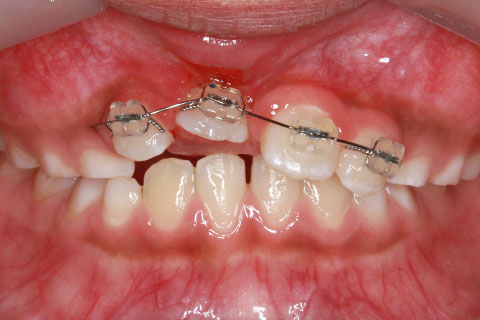

子供の乳歯が抜けて、かなりの時間が経つのに永久歯が生えてこないと心配して来院される親御様は多くいらっしゃいます。この場合、レントゲンにて確認すると大体の場合、もうしばらく待っていれば生えてくるであろうと予測がつきます。しかし、稀に歯の位置異常により、埋まったままの状態で生えてこないことがあります。この場合、待っていても生えてきませんので、矯正力により歯を引っ張り出す必要があります。これを矯正学では開窓・牽引術と呼び、歯肉を切開して、歯の表面を露出させ、そこに矯正器具を付けて、良好な位置まで引っ張り出すという治療法です。

開窓・牽引の症例